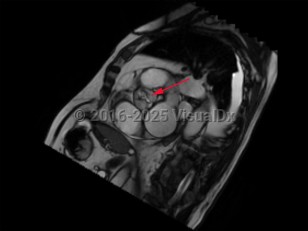

Cardiac tamponadeCardiac tamponade